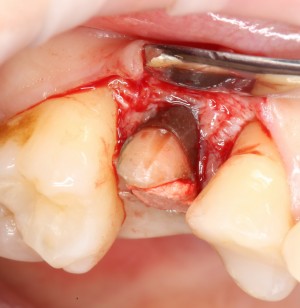

Первое, с чего начинается удаление зуба — это разрез. С помощью скальпеля и периотома отделяется круговая связка зуба. Конкретно в этом случае важно еще увидеть границы лунки, чтобы понять пределы аугментации:

Ну и, зуб проще удалить, если ты видишь, что от него осталось. Что мы и делаем:

Вместе с зубом удаляется прикорневая гранулема. После того, как из лунки удалены все патологически измененные ткани, можно подумать о том, как сохранить объемы альвеолярного гребня в этом участке для будущей имплантации.